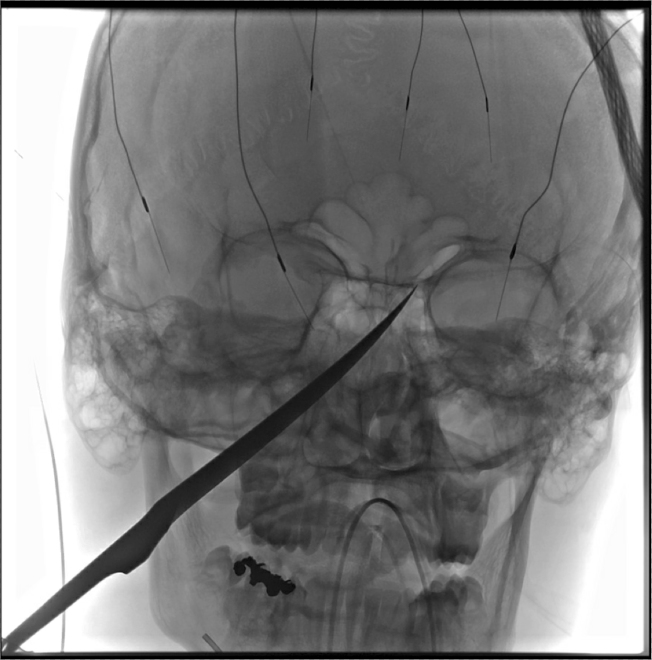

10吋長刀刺穿臉 男孩幸運存活

堪薩斯州一名15歲男孩被一把長刀刺穿臉,但幸運存活,醫生表示,他實在相當幸運。

吉米‧羅素(Jimmy Russell)表示,她的兒子葛瑞格(Eli Gregg)13日傍晚,在位於堪薩斯市南邊約90英里處瑞德費勒城的家外面玩耍,突然就聽見兒子尖叫聲音,她隨即跑出屋外,發現一把10吋刀子插進葛瑞格臉部眼睛下方,於是趕緊打電話給911。

羅素說,兒子當時情況非常危急。大刀插進他的頭骨並延伸到大腦下方。同時,刀的尖端部分正推進為大腦提供血液的頸動脈。身體幾乎無法承受如此大的壓力,但他卻在這個情況下倖存。負責將刀取出的醫生艾柏索爾(Koji Ebersole)說,他原本不認為葛瑞格能存活。

外科醫生團隊合作一項錯綜複雜的計畫,在意外發生的隔天14日上午取出插在葛瑞格臉部的刀。他們先為可能的大出血進入腦部而提前做準備,但手術進行順利,動脈保持完整。

經過24個小時的手術後,葛瑞格能夠說話並解釋意外當時狀況。他預定於17日出院。羅素說,兒子表示自己將遠離尖銳物品。目前情況良好,應該可以完全康復,「這幾乎是個奇蹟。非常令人驚奇。」